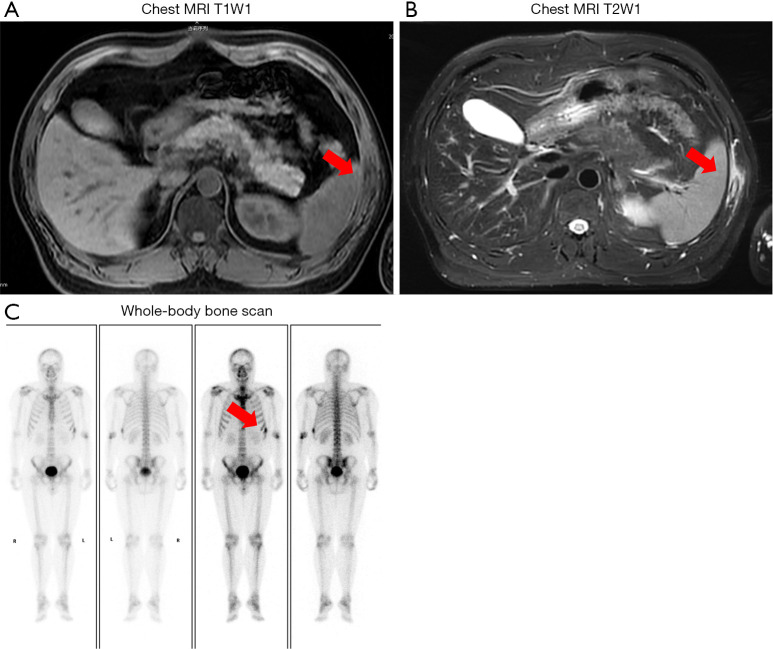

Conclusions: LCH can involve various organs and systems, presenting with diverse clinical manifestations; in particular, rib Langerhans cell histiocytosis (RLCH) primarily manifests as asymptomatic or mildly painful bone swelling. Computerized tomography (CT) imaging of RLCH typically reveals localized masses and focal bone destruction, with or without surrounding soft tissue invasion. Conversely, magnetic resonance imaging provides a clearer assessment of lesion size and the extent of adjacent soft tissue involvement, offering advantages in guiding surgical excision. Diagnosis requires correlation with pathological and immunohistochemical results. For single-system, single-site (SS-s LCH), R0 surgical resection is feasible; however, single-system, multi-site (SS-m LCH) cases necessitate combined chemotherapy or targeted therapies. Overall, the treatment outcomes for this disease remain reasonably favorable.